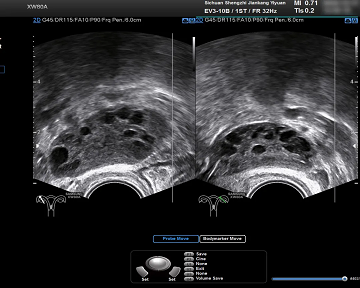

2、妇科超声检查:核心检查之一(建议在月经第3-5天进行,月经不规律可随时进行)。一侧或两侧卵巢直径2-9mm卵泡≥12个,或卵巢体积≥10cm³,即多囊卵巢样改变。

B超下多囊卵巢样变化

💡注:随着超声技术的进步,一些新的指南(如多囊卵巢综合征中西医结合诊疗指南) 2024版)建议阈值可提高到20个,具体要听从医生的建议。

此外,多囊卵巢的形态(PCOM)女性在月经初潮8年内比较常见,因此,青春期女性不建议根据超声检查PCOM来诊断PCOS。